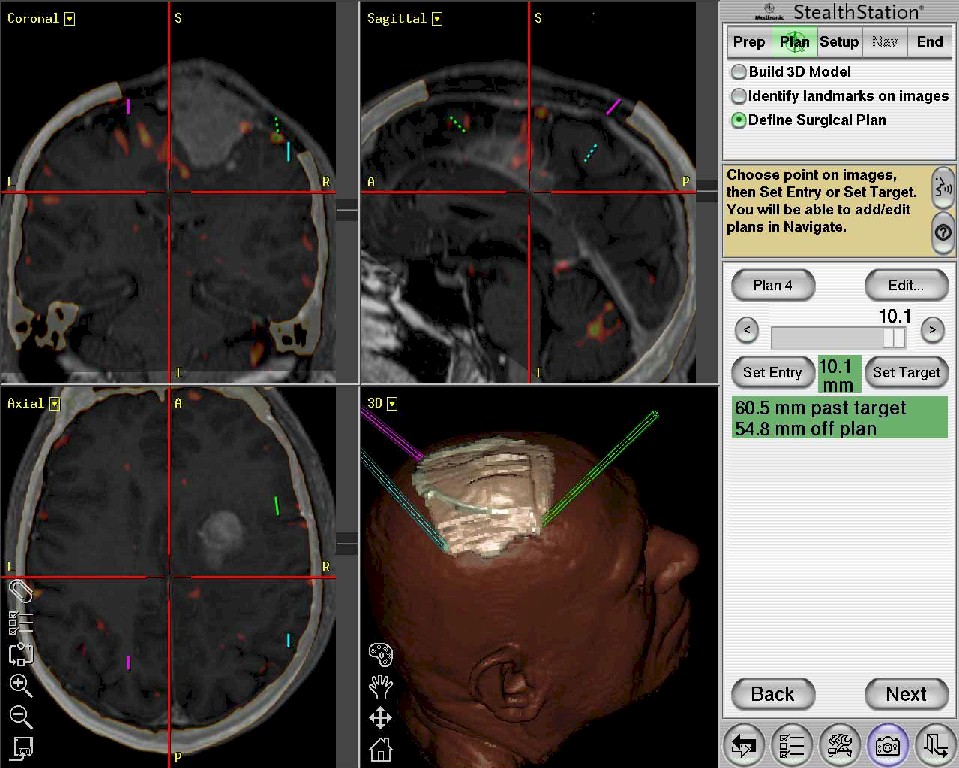

Neurochirurgia

Chirurgia tumori